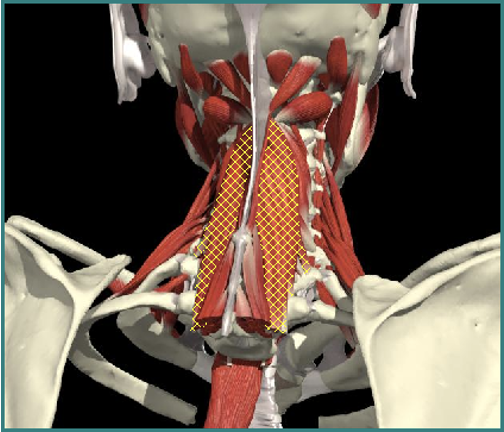

Torticollis

Cervical Dystonia

Muscle Selection

Muscles Attached to Spine

- Ipsilateral rotation

Longissimus cervicis

Contralateral rotation

Semispinalis cervicis

Scalenus anterior